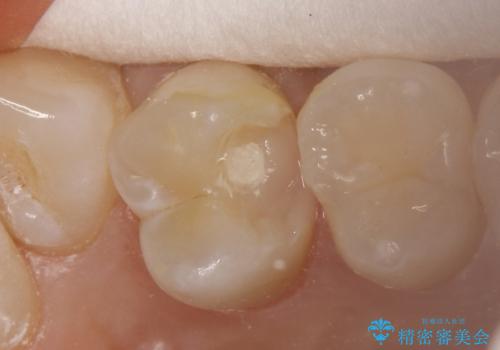

- 神経を温存し、セラミックインレーによる修復をおこなった。

詰め物の種類:e.max press